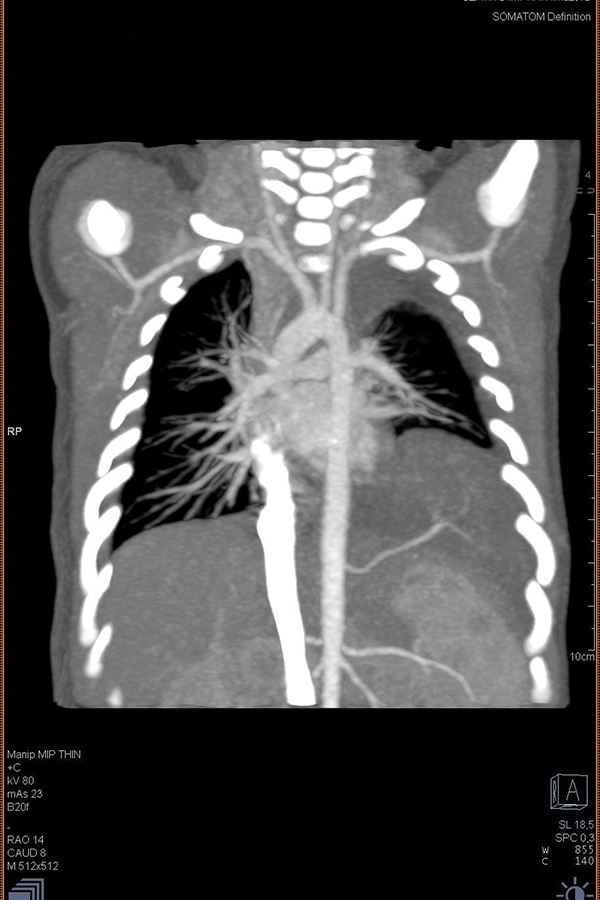

На основании рентгенограмм предположили секвестрацию легкого – достаточно редкий порок развития, при котором часть аномально развитой легочной паренхимы отделяется от легкого. «Лишний» участок легочной ткани не наполняется кислородом, «не дышит». Кровоснабжение секвестра, в отличие от других аномалий развития легких, осуществляется изолированным сосудом, отходящим непосредственно от аорты.

Компьютерная томография подтвердила данный диагноз. Из-за необычного симптома – внутриутробного скопления жидкости в плевральной полости – дополнительный кровеносный сосуд и большой секвестр невозможно было обнаружить при УЗД до родов.